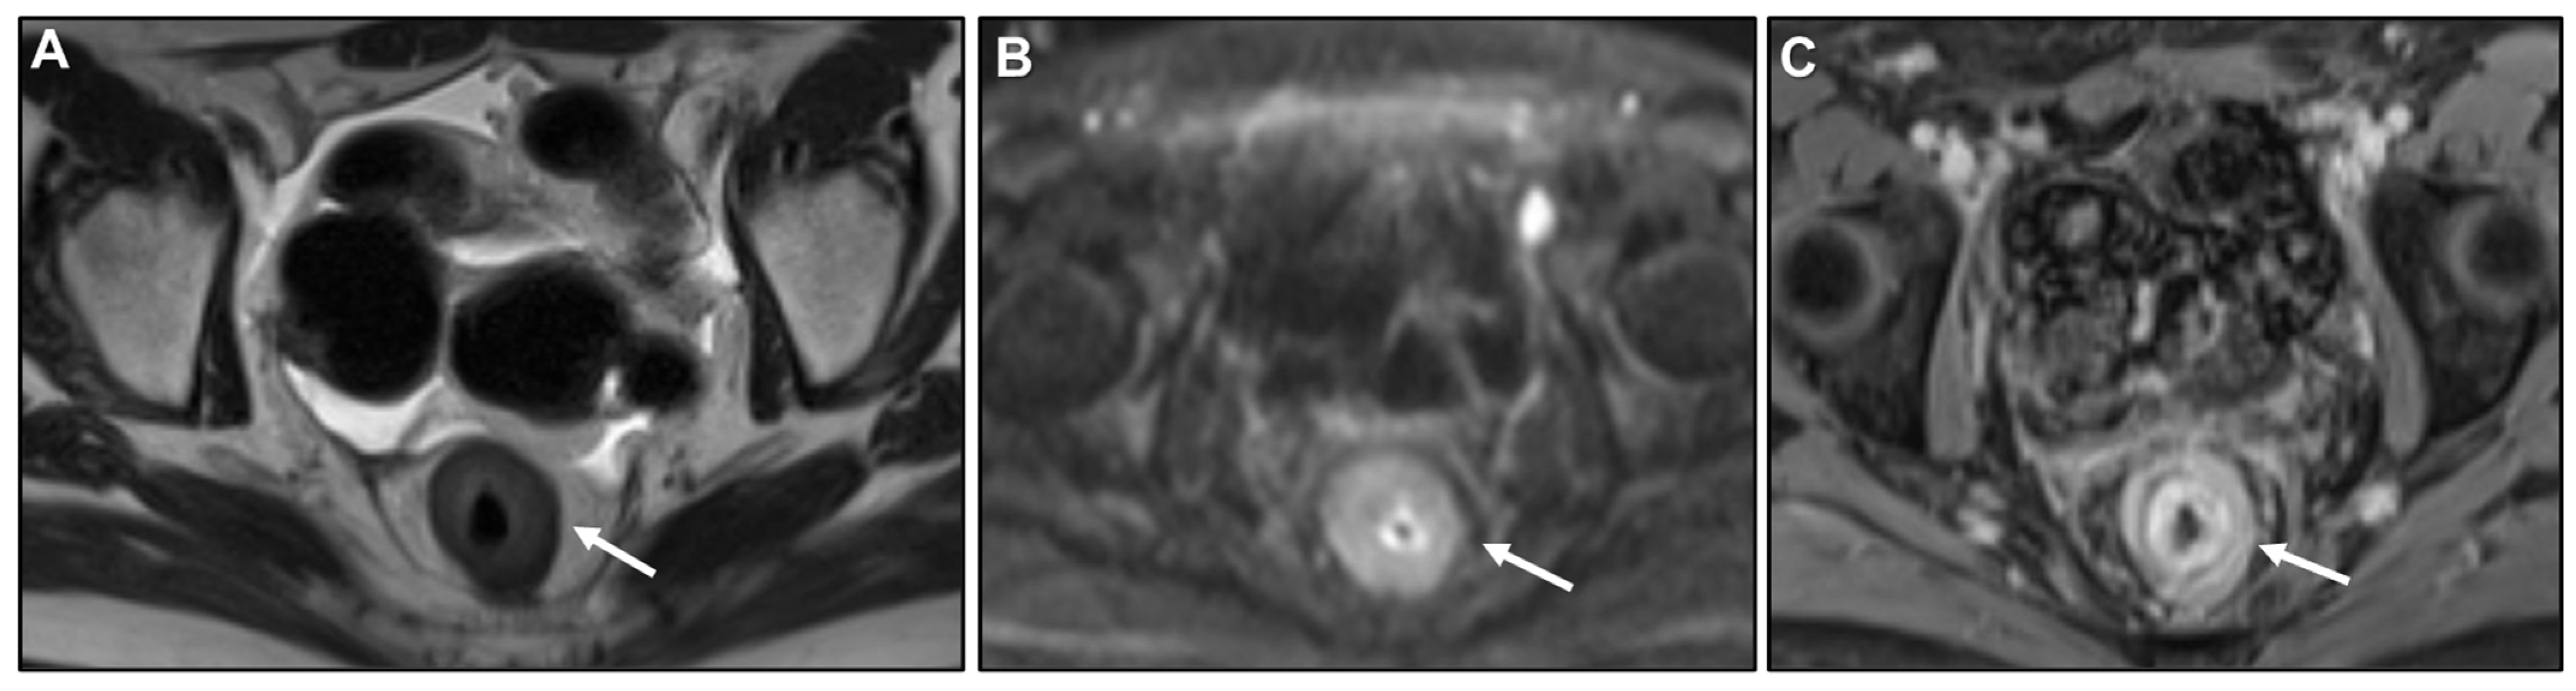

Concentric Ring Pattern